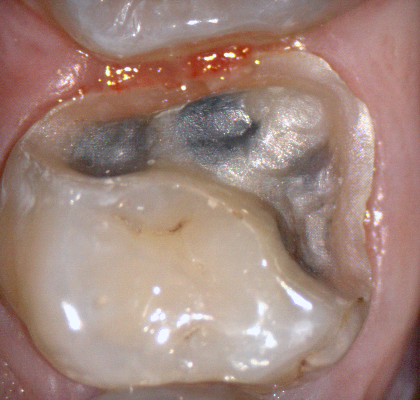

The following pictures depict the sequence of burs we recommend that you use to finish a preparation quickly. While patient is getting numb, take a quick look at the clearance you will need to reach proper material thickness. Once the quadrant is isolated with isolite and optragate, take an occlusal router bur and create a trough to gain the proper depth. Follow that with a flat disk, and you can quickly reduce the occlusal height.

A shoulder bur of .8 mm thickness can help you reduce the interproximal areas as well as the buccal and lingual margin lines. Before finishing the prep, place hemostatic agent like expasyl in the sulcus and place retraction cord. while it is setting, check your reduction. If you need more space, now is the time to reduce some more.

Once you have adequate clearance, retraction, and hemostatis, you can readily image and find your margins in the CAD software